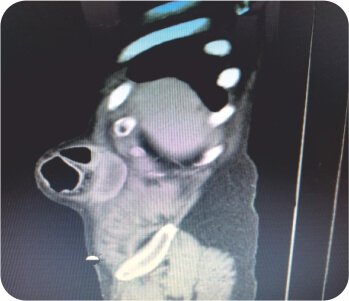

MDCT the investigation of choice, which diagnosed an enterocoel with mesentric stranding and dilated bowel with a 6x 4 cm defect, fracture right 7,8, and 9 ribs and old healed left 8&9 ribs no pneumothorax or hemothorax.

Sagittal CT scan showing Hernia

Dilated loop of bowel